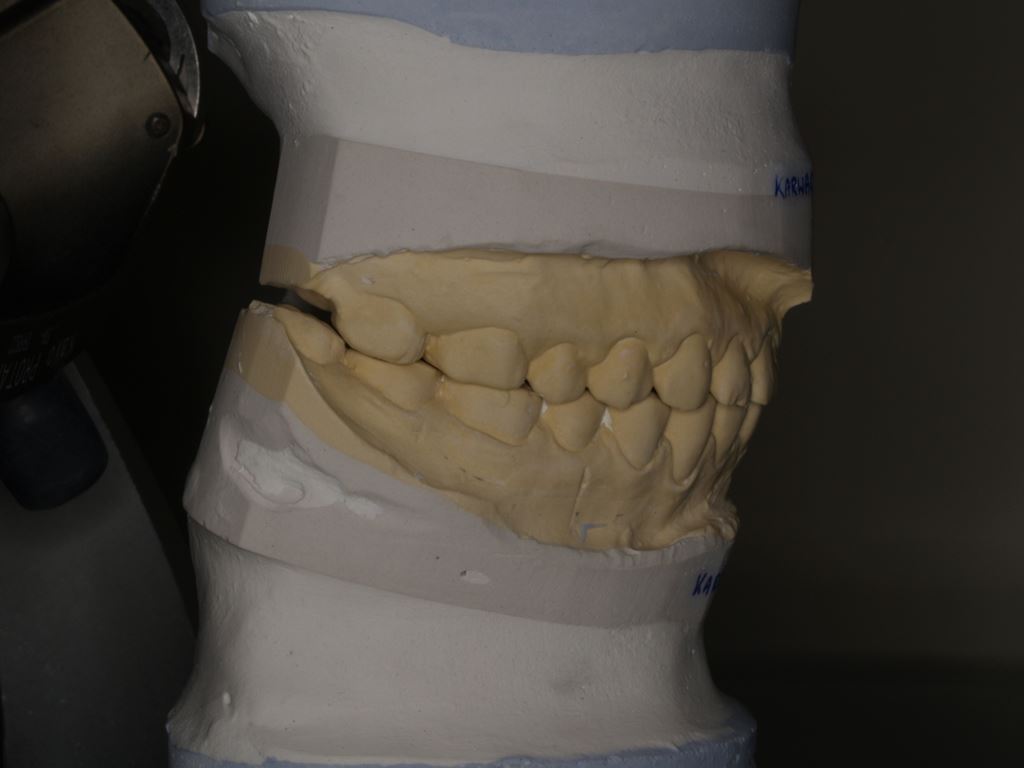

Wykonano także modele diagnostyczne zaartykulowane w relacji centralnej (RC), którą zarejestrowano ze względu na zwiększone napięcie mięśniowe z wykorzystaniem deprogramatora Koisa (ryc. 13-15), oraz zdjęcie pantomograficzne (ryc. 16) i cefalometryczne. Analiza modeli w RC wykazała przesunięcie żuchwy w kierunku doprzednim w stosunku do pozycji maksymalnego zaguzkowania i przedwczesne kontakty funkcjonalne na zębach bocznych, co tłumaczyło obecność odprysków szkliwa na brzegach siecznych górnych zębów (szczególnie wyraźne na zębie 12) (ryc. 14, 17). Na modelach wykonano studium funkcjonalne mające na celu określenie, w jaki sposób można odtworzyć prawidłową funkcję, tzn. uzyskać prawidłowy nagryz pionowy i poziomy oraz prowadzenie przednie (ryc. 18-20).

Uzyskanie prawidłowych relacji pomiędzy zębami przednimi górnego i dolnego łuku zębowego wymagało zwężenia dolnego łuku i cofnięcia zębów przednich w kierunku dojęzykowym. Zwężenie poprzez wykonanie strippingu nie byłoby wystarczające, dlatego zaplanowano usunięcie jednego z dolnych zębów siecznych przyśrodkowych. Osiągnięta w ten sposób zmiana relacji zębów umożliwiała odtworzenie warunków zwarciowych zgodnie z koncepcją okluzji wielostronnie chronionej (ang. mutually protected occlusion).